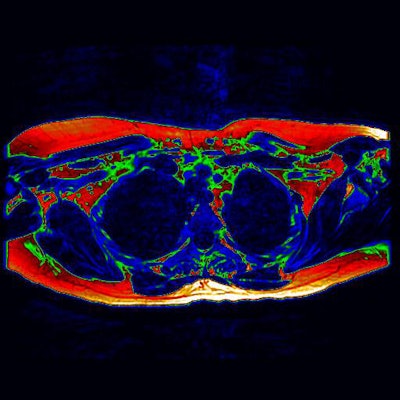

The digitally enhanced axial MRI of the upper chest (as if viewed from the feet) shows area of potential brown fat (green). Image courtesy of the University of Warwick.Brown fat has drawn the interests of researchers due its ability to use energy and burn calories, thus controlling weight.

Unlike PET data, which only displays activity, MRI shows brown fat content whether active or not to provide detailed insight into where it can be found in the adult body. This information could prove vital in the creation of future therapies that seek to activate deposits of brown fat.